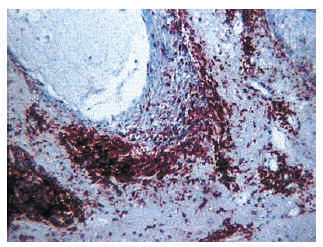

Las formas de mucinosis folicular primaria localizada y de mucinosis folicular primaria difusa fueron similares histológicamente. Se caracterizaron por abundantes depósitos de mucina en el folículo y una intensa destrucción folicular (figs. 6 y 7), que en ocasiones se acompañaba de granulomas foliculares secundarios. El infiltrado inflamatorio era escaso, de distribución superficial y perifolicular, sin atipias ni epidermotropismo. Los eosinófilos fueron escasos o ausentes en el infiltrado.

Fig. 7.--Depósitos de mucina marcados con hierro coloidal.